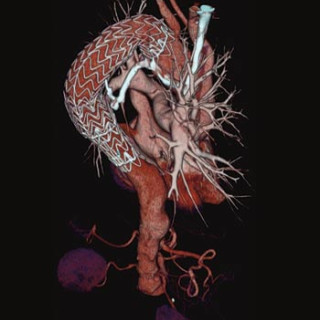

Nevroradiologi omhandler bildediagnostikk av og bildeveiledet intervensjon i sentralnervesystemet. Pasientene er i alle aldersgrupper, og flere av sykdommene er kroniske. Kunnskap om barnenevroradiologi er vesentlig for forståelsen av mange lidelser hos voksne. De viktigste bildediagnostiske hjelpemidlene (modalitetene) er CT, MR og angiografi, i tillegg til vanlig røntgen, myelografi, ultralyd, scintigrafi og positronemisjonstomografi (PET). Faget er en naturlig subspesialisering fra generell radiologi, med bakgrunn i behovet for oppbygging av kompetanse om og utvikling av høyspesialiserte...